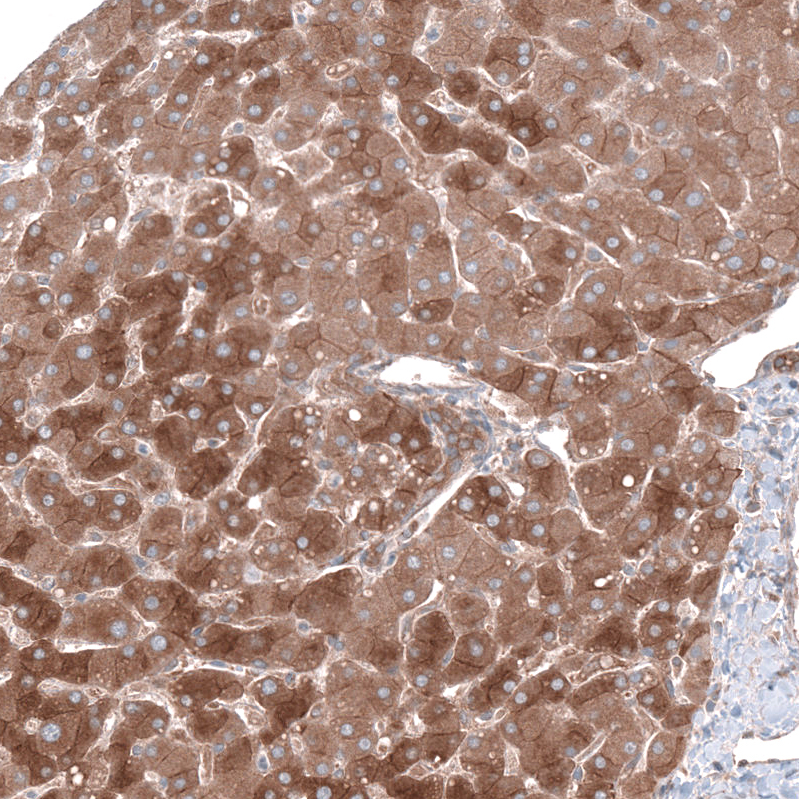

Immunohistochemical staining of human skeletal muscle shows strong cytoplasmic positivity in myocytes.